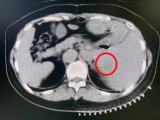

术中影像

介入科团队在CT影像监测与引导下,准确将消融探针插入肿瘤内,将肿瘤组织迅速冷却至-196℃,使癌细胞迅速降温,形成的“冰球”效应能够让医生直观监控,精细控制冷冻范围,确保完全覆盖肿瘤病灶并进行杀伤,冰冻后迅速复温至80℃,导致组织内肿瘤细胞脱水破裂,肿瘤细胞迅速死亡。